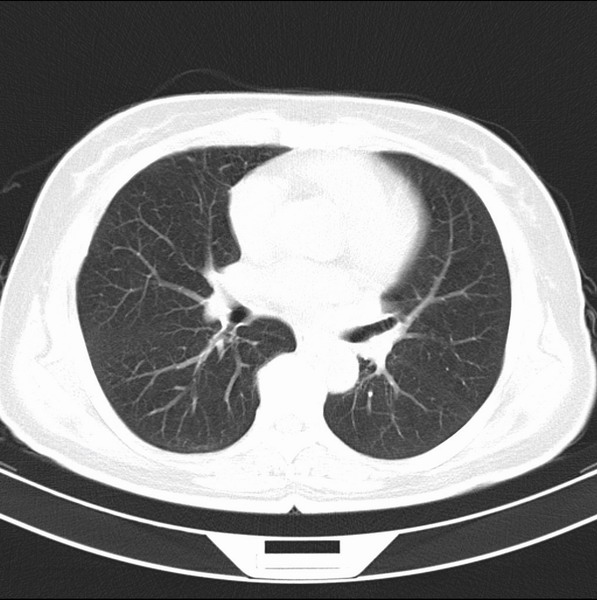

女、63

咳嗽、胸痛四个月

考虑左下肺中央型肺癌

支持左下中央型肺癌伴阻塞性炎症不张。

包绕左下肺基底段的不规则的软组织肿块,段支气管腔变形、狭窄及阻塞性炎症,病变区不规则强化,又是老年女性支持楼上看法。

典型病例:左下肺基底段中央型肺癌,相应支气管狭窄并阻塞性炎症